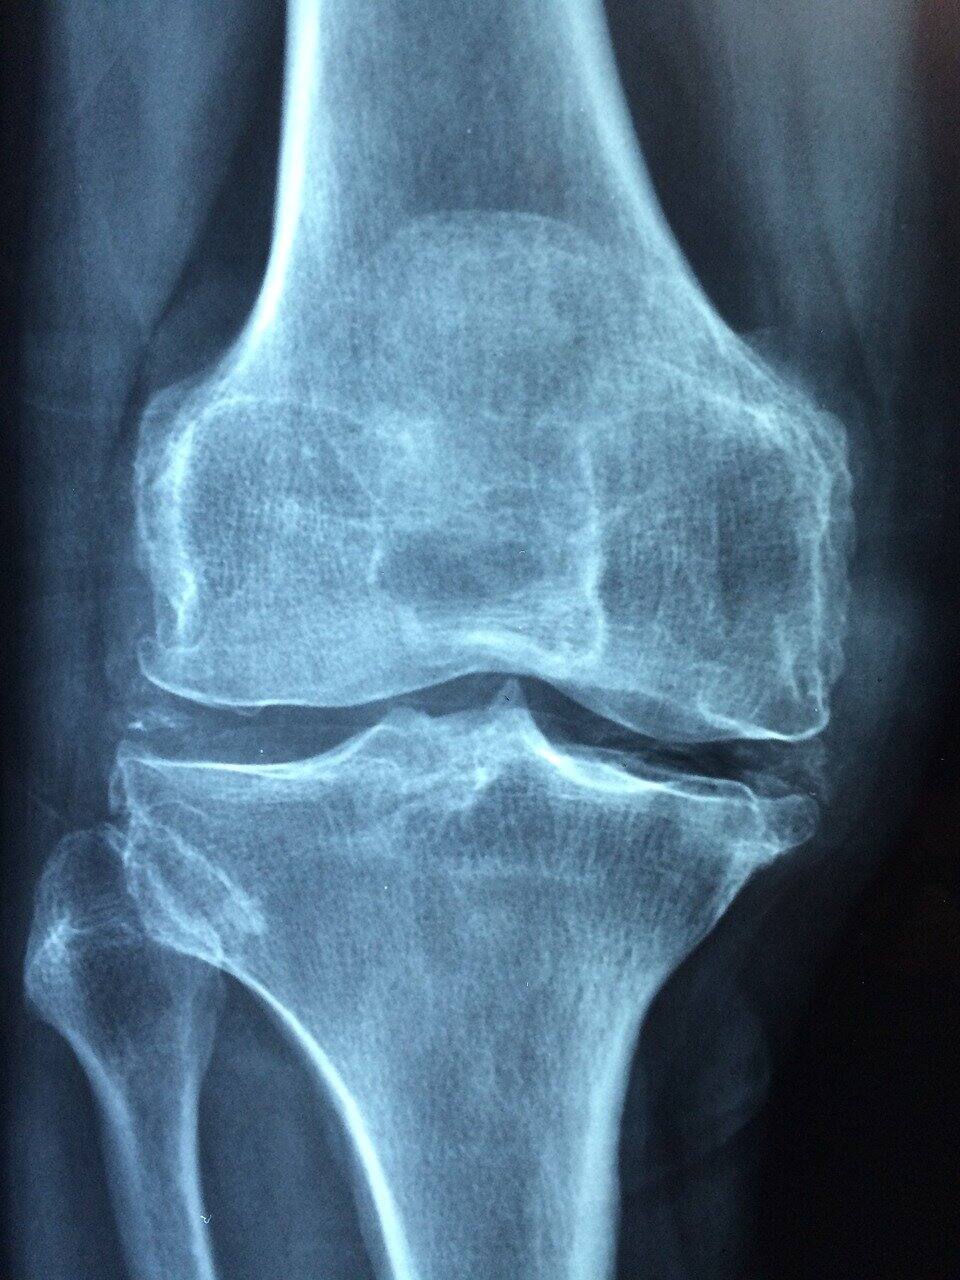

ఆర్ధరైటిస్ ఉన్న వారు ఈ ఆహారాలు తినకూడదు

చలికాలంలో ఆర్ధరైటిస్‌తో బాధపడుతున్నవారికి నొప్పులు మరింత ఎక్కువవుతాయి.

కొన్ని ఆహారాలు తినడం కీళ్లనొప్పులు, వాపులు మరింత పెరిగే అవకాశం ఉంది.